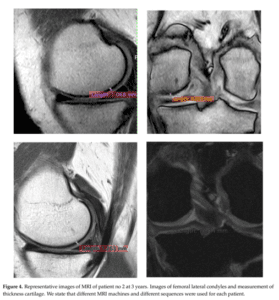

Specialistii dar si pacientii cu “experienta” in artroza, pot identifica castigul de grosime a tesutului articular comparand imaginea de sus cu cea de jos respectiv aceeasi incidenta a articulatiei investigate RMN inainte de administrarea terapiei Rigenera in artroza si apoi la 3 ani dupa tratament.

- Fiecare calup de imagini reprezinta cate un pacient investigat cu incidenta frontala si laterala. Detalii suplimentare in marginea inferioara a fiecarei imagini - interpretarea imaginilor se face pe 1/2 stanga sus versus jos si 1/2 dreapta sus versus jos.